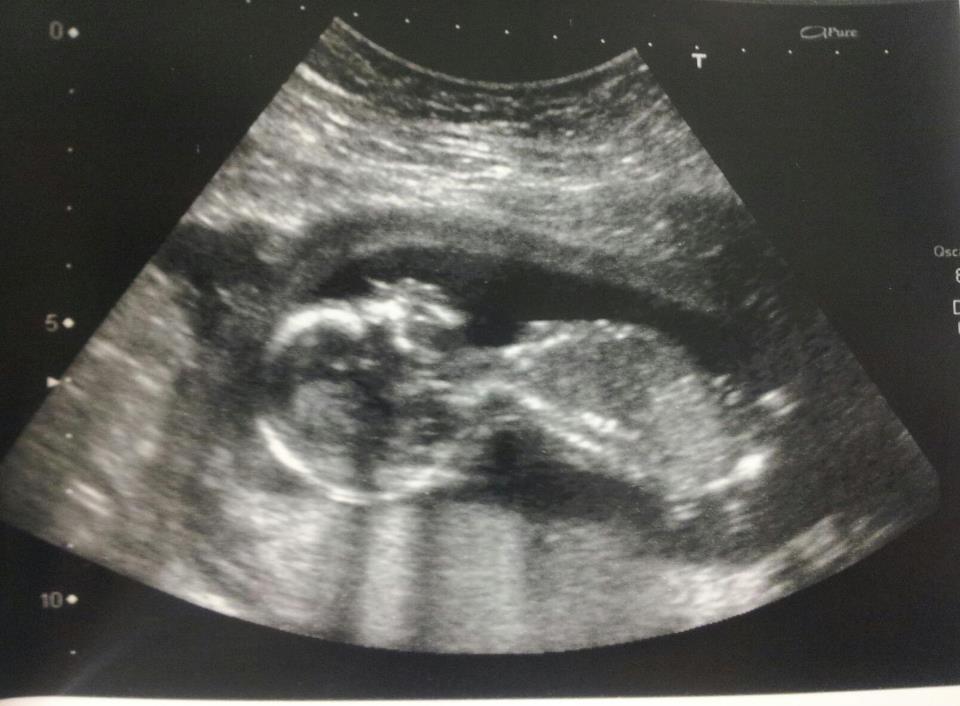

15 week scan...

Attachment 7512